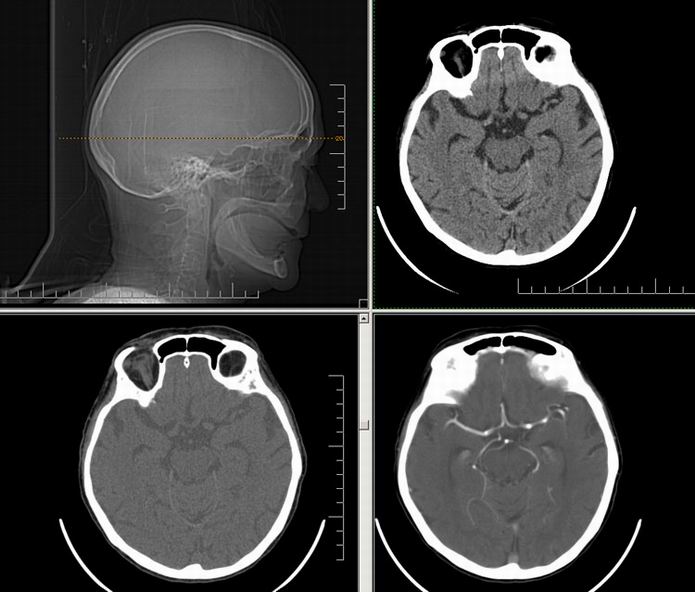

Est ce que qqun a des coupes axiales de crâne pour m'aider à réviser mon anatomie. Merci

Pour compléter tes révisions, Poupette vient de nous faire parvenir ces planches bien utiles: Planches de coupes axiales cérébrales, dans la rubrique COURS / ANATOMIE